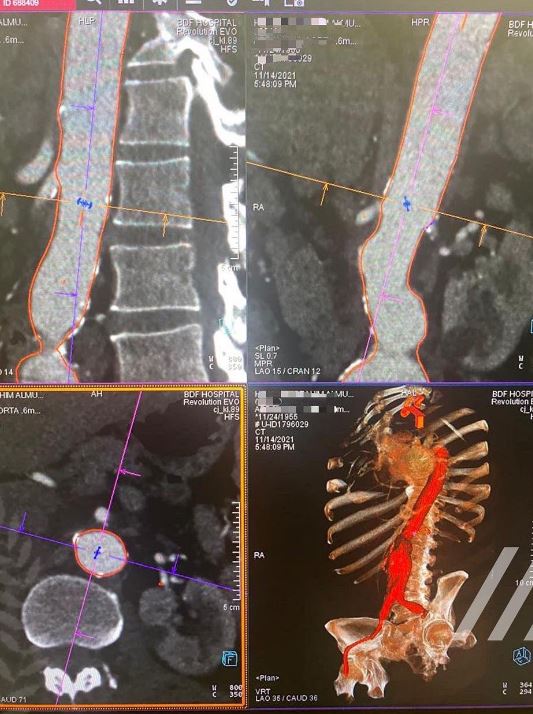

A TEAM of surgeons at BDF Hospital has succeeded in treating a 66-year-old patient who suffered from abdominal aortic aneurysm by using a new technique, revealed vascular and endovascular surgeon Dr Martin Maresch.

Used for the first time, the surgery required a small incision through an artery in the abdomen .